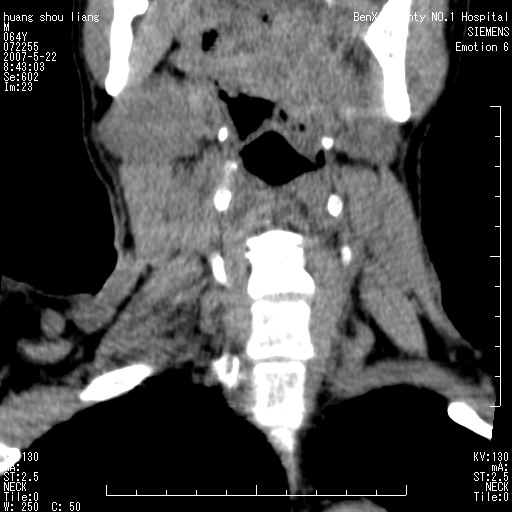

男性,64岁。颈部包块8年。最近增大。

对不起大家,可能是片子发太多有点乱,正常腮腺在下颌角的外侧,颌下腺在下颌体的中部内侧,本例在下颌角内侧偏下,和腺体一点关系都没有,从vrt和mpr上可以很明显看出来,再者肿块是好多粘连在一块的,大家在仔细看看,左侧可能也是吧,我还是考虑为肿大的淋巴结融合在一块,但性质??????

右侧腮腺下部均匀软组织密度肿块,外形不规则,与周围组织分界清晰,考虑右侧腮腺混合瘤或多形性腺瘤。

多考虑颌下腺混合瘤恶变,建议进一步检查,另外楼主重建图像很漂亮。

大家好,病理结果出来了,如大家所说,颌下腺混合瘤。

唉,解剖没学好吧,我诊断错了,不过还是有些不理解回去我在多看看书,谢谢大家的参与,以后我还会奉献好的病例。